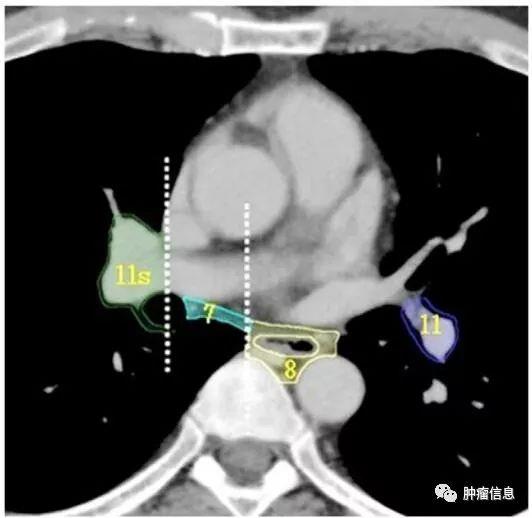

第7组淋巴结区

隆突下淋巴结:隆突下3cm内,与肺内下叶支气管、动脉无关。上界:气管隆突下界:左侧为下叶支气管上缘、右侧为中间支气管下缘

第8组淋巴结

食管旁淋巴结:自隆突下沿食管延伸至膈肌食管裂孔。上界:左侧为下叶支气管上缘、右侧为中间支气管下缘下界:膈肌

第11组淋巴结

第11组即肺叶间淋巴结,位于支气管分叉处。左侧第11组淋巴结位于第二隆突的下方。右侧的第11组淋巴结又区分为11s(右侧上叶支气管和中间支气管之间)和11i(右侧中叶支气管和下叶支气管之间)。